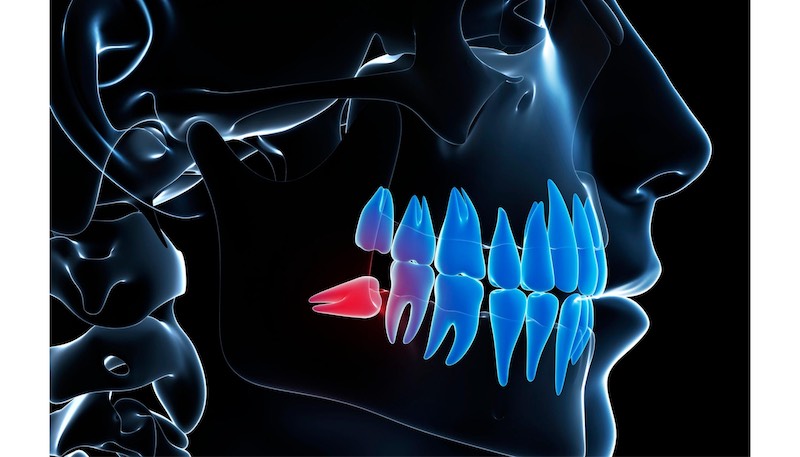

Need wisdom teeth removal in Chattanooga? Dr. Fitzhugh's specialized surgical training from The Foundry means most patients can have even complex, impacted wisdom teeth removed in-house. Learn about the process, recovery, and why patients are "blown away" by his skill...

Wisdom Teeth Removal in Chattanooga: Expert Care at Harrison Family Dentistry